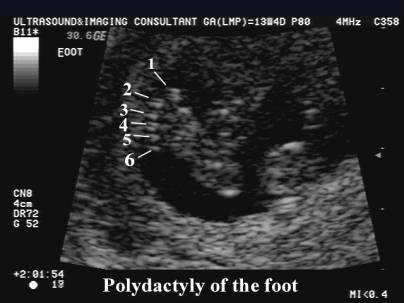

What is Polydactyly?

extra fingers or toes.

Polydactyly

Polydactyly